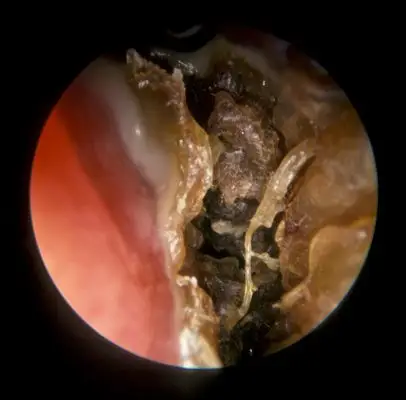

鼻窦炎症状图片 (44)